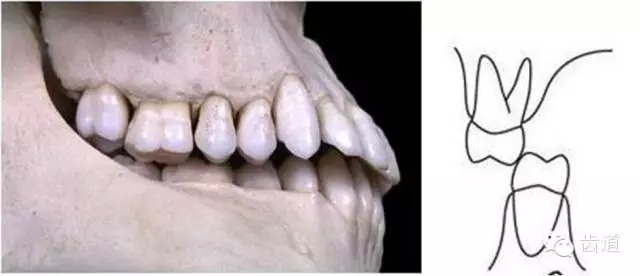

上頜第一磨牙的近中頰尖位于,下頜第一磨牙的頰溝遠中

典型面形為下頜前突面形

前牙有切道與切道斜度

切道:下前牙切緣前伸的軌道

切道斜度:切道與水平面所成的角度